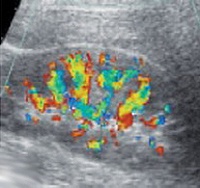

N18 Хроническая почечная недостаточность